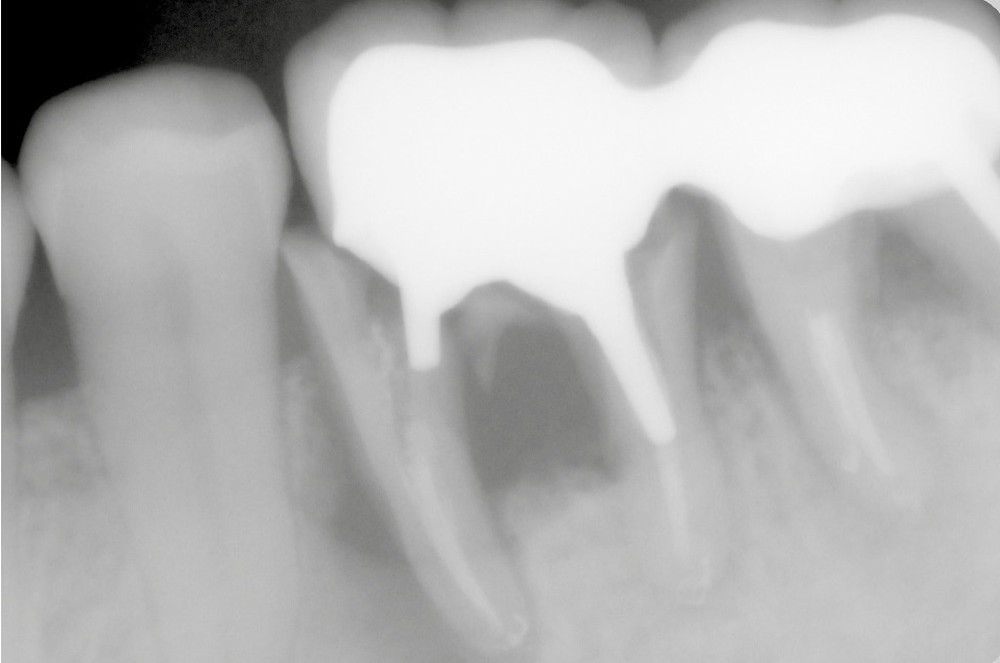

Il est communément admis que l’évaluation des parois dentinaires résiduelles après préparation périphérique externe, est le facteur principal de choix de la RCR [2].

Ainsi, les RMIPP sont indiquées lorsque la dent présente 2,5, voire 2 parois, et que la mise en place d’un champ opératoire (digue) est possible pour assurer les procédures de collage dans les meilleures conditions d’étanchéité.

En deçà de 2 parois résiduelles ou en cas de limites cervicales trop profondes pour garantir une parfaite isolation, l’inlay-core trouve traditionnellement son indication.

L’application stricte de ces règles élémentaires oriente donc préférentiellement, dans le cas de perte tissulaire modérée ou importante, vers la réalisation d’inlay-core (fig. 1a-b).